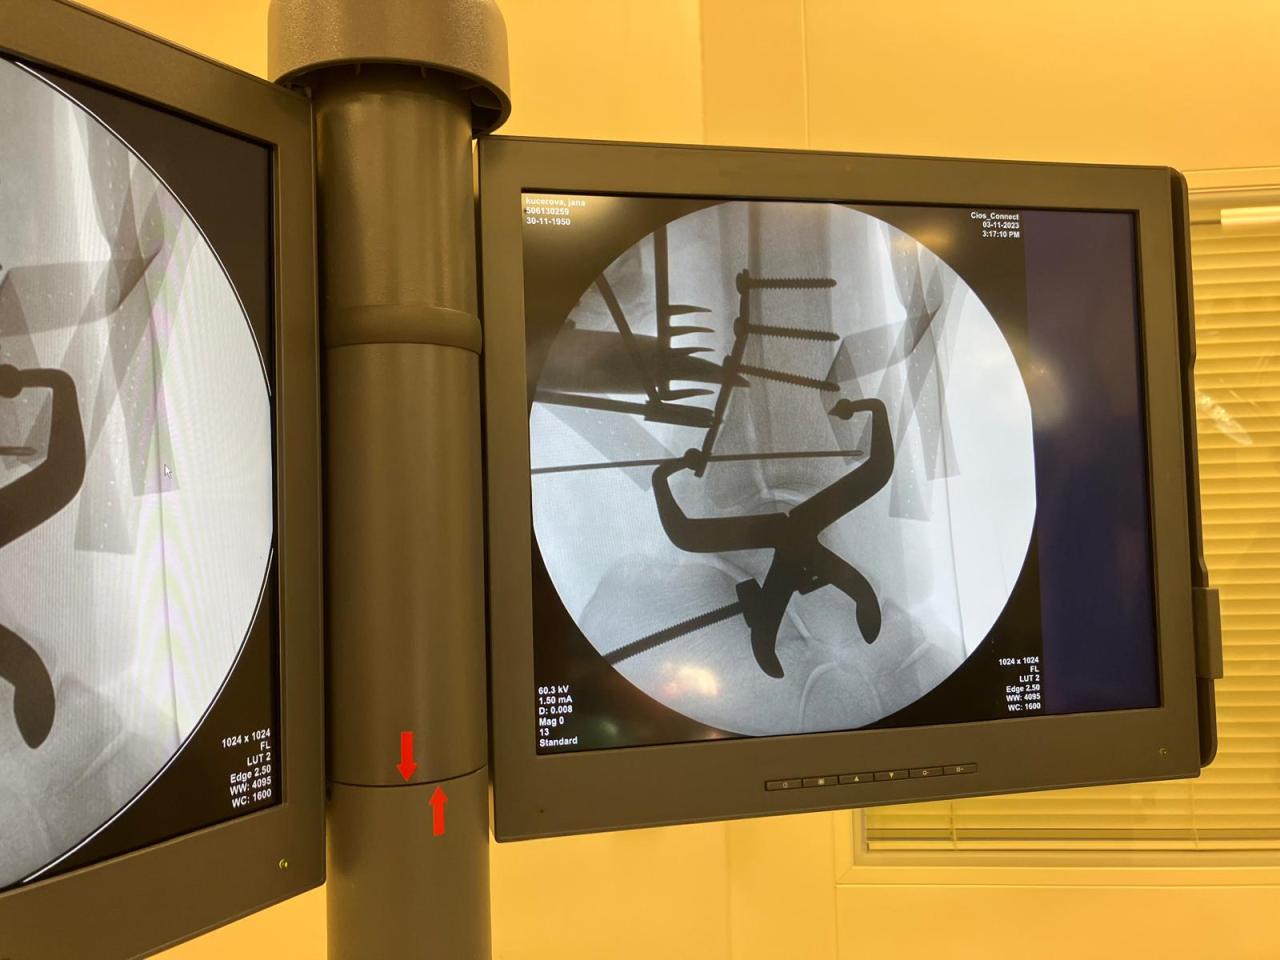

Moderní vybavení, šikovné ruce zkušených chirurgů, anesteziologové, spolehlivé sestry i další zdravotníci... To je dokonalá souhra, která je potřeba k úspěšně provedenému chirurgickému zákroku.

V čáslavské nemocnici podstupuje operační zákroky několik pacientů denně. Zajímá vás, jak to při takové operaci vypadá? Podívejte se na pár zajímavých záběrů z operačního sálu.